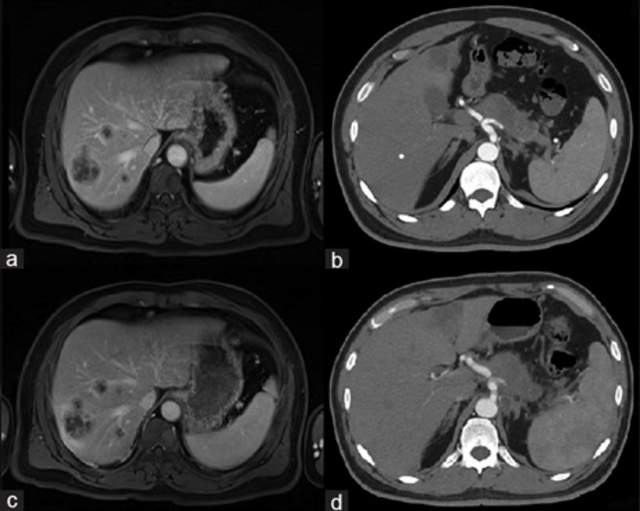

这位患者确诊为胰腺导管腺癌(PDAC)并已发生肝转移,影像检查显示胰腺肿瘤体积达6cm×2.5cm×3cm,肝脏最大转移灶直径3.5厘米。

由于肿瘤已无法手术切除,且患者拒绝传统化疗方案,医疗团队为其制定了CAR-NK细胞免疫治疗方案。令人振奋的是,治疗后患者的胰腺原发灶和肝脏转移灶均得到有效控制。